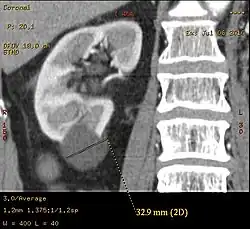

Category IIF

A Bosniak category IIF cyst. This one is 3 cm wide, with calcifications within its wall, seen as very radiodense (white in this presentation) areas in its margins. There is also a septation which is calcified. Yet, the cyst does not show enhancement (uptake of contrast).